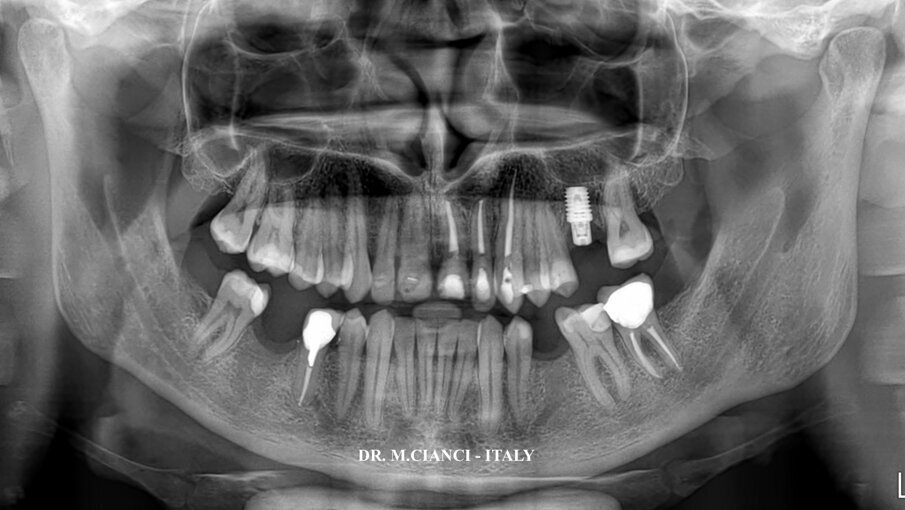

Dopo l’intervento è stata eseguita una ortopantomografia (OPT) di controllo (Fig. 12) e dimesso il paziente con un protocollo farmacologico di 2 grammi di Amossicillina più Acido Clavulanico per 6 giorni e un mantenimento igienico con clorexidina 0.2% per 10 giorni. Il controllo radiografico endorale a 5 mesi della chirurgia rivela un perfetto mantenimento dei livelli di osso peri-implantare (Fig. 13). Avvenuta la osteo-integrazione dell’impianto la protesizzazione sarà completata con una ceramica integrale avvitata14.

Fig. 12 - Opt post-chirurgica.